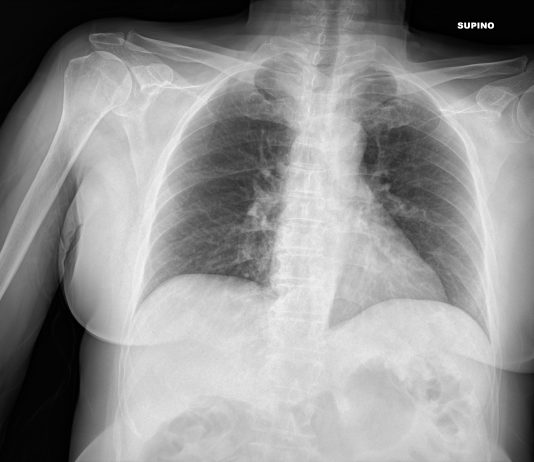

65-years-old male

patient presented to the ED with fever and cough.

Blood test: C-PR 70,99 (< 5) LDH 326 (< 225).

Chest radiography: